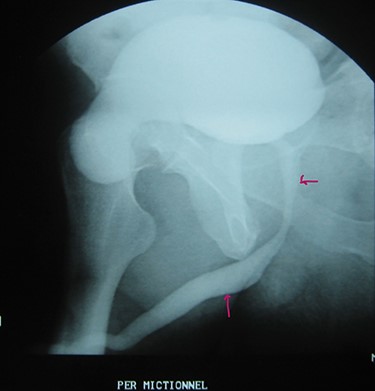

A 72-year-old man with a history of controlled diabetes and hypertension presented to our department with right inguinal swelling and intermittent lower urinary tract symptoms (LUTS) with pollakiuria, dysuria, prolonged micturition time and a sensation of a full bladder after micturition. He reported nausea, vomiting and right lower quadrant paint. The patient also reported having to manually compress the scrotum in order to empty the bladder. Physical examination revealed a slightly painful on palpation and reducible 6 cm right inguinal hernia extending into the right hemiscrotum. The body mass index of the patient was 31.4 kg/m2. His PSA was 4.3 ng/ml. On uroflowmetry, maximum flow rate (Qmax) was 13 ml/s and the voided volume was 180 cc. The uroflow curve was flat. The Bacteriological examination of urine was negative. Retrograde urethrocystography revealed right inguinal hernia containing a portion of the urinary bladder (Figs 1,2). He also had an intravenous urography in order to study the upper urinary tract and to have an idea of the renal function. This radiological exploration confirms the data of the retrograde urethrocystography and illustrates well the bladder hernia. However, a moderate left hydronephrosis with a nonobstructive pyelic calculus of 1.5 cm was observed on intravenous urography (Figs 3,4). Intraoperative findings revealed a direct right inguinal hernia with complete herniation of bladder into the scrotum. The bladder appeared healthy with no signs of injury and was restored to its normal anatomical position without resection. The hernia was repaired with a biologic mesh by the Lichtenstein technique. The patient had an uneventful postoperative course. Concerning his pyelic calculus problem, shock wave lithotripsy sessions were scheduled.

Intravenous urography: moderate left hydronephrosis and bladder addition image.

Intravenous urography: nonobstructive pyelic calculus of 1.5 cm.